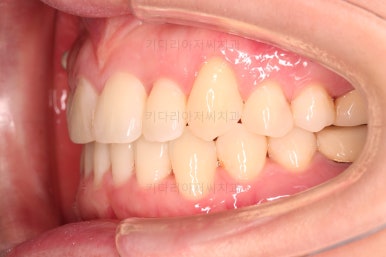

부산치과교정 키다리아저씨치과 초진 시 입안의 모습입니다.

확연히 좌우의 삐뚤어진 정도가 차이나죠.

덧니도 좌측(사진에서 보면 오른쪽) 위아래만 있는 상태고요.

좌측으로 삐뚤어져서 앞니도 좌측으로 쏠려 있는 상태였습니다.